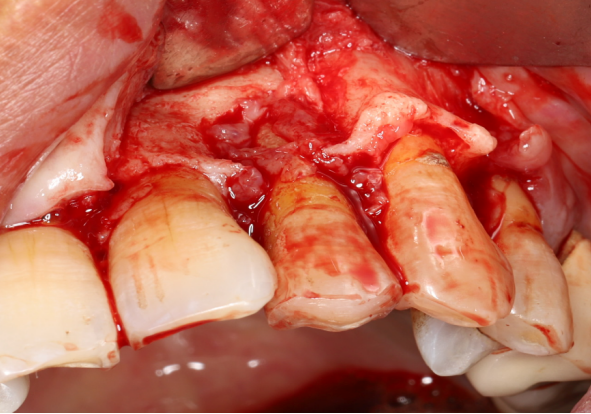

使用12#镰形刀片沿21、22、23做龈沟内切口,于24近中做垂直附加切口。

翻开全厚粘骨膜瓣,暴露22颊侧牙槽骨,微创拔除22。

搔刮22拔牙创,暴露22牙槽骨表面,开放骨髓腔。